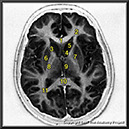

N1A5P8

22